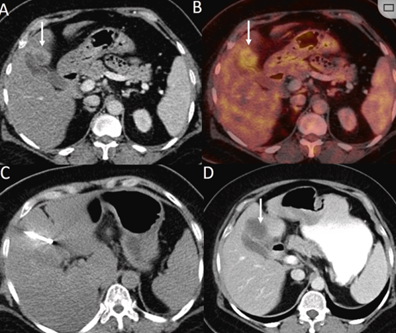

CT引导的冷冻消融

冷冻消融胆囊附近肿瘤病灶

(A)动脉期 MRI 显示胆囊附近有外周增强病变(箭头)。

(B)手术过程中 CT 显示冷冻探针位于病灶内。

(C)消融后,术后 1 个月CT 显示完全消融(箭头)。

冷冻消融肝包膜下肝细胞癌

(A)动脉期CT图像显示有一个包膜下结节(箭头)。

(B)门静脉期CT图像显示病灶区(箭头)。

(C) 在手术过程中的CT显示一个冷冻探针位于病灶内。

(D)消融后,术后1个月影像CT显示完全消融。